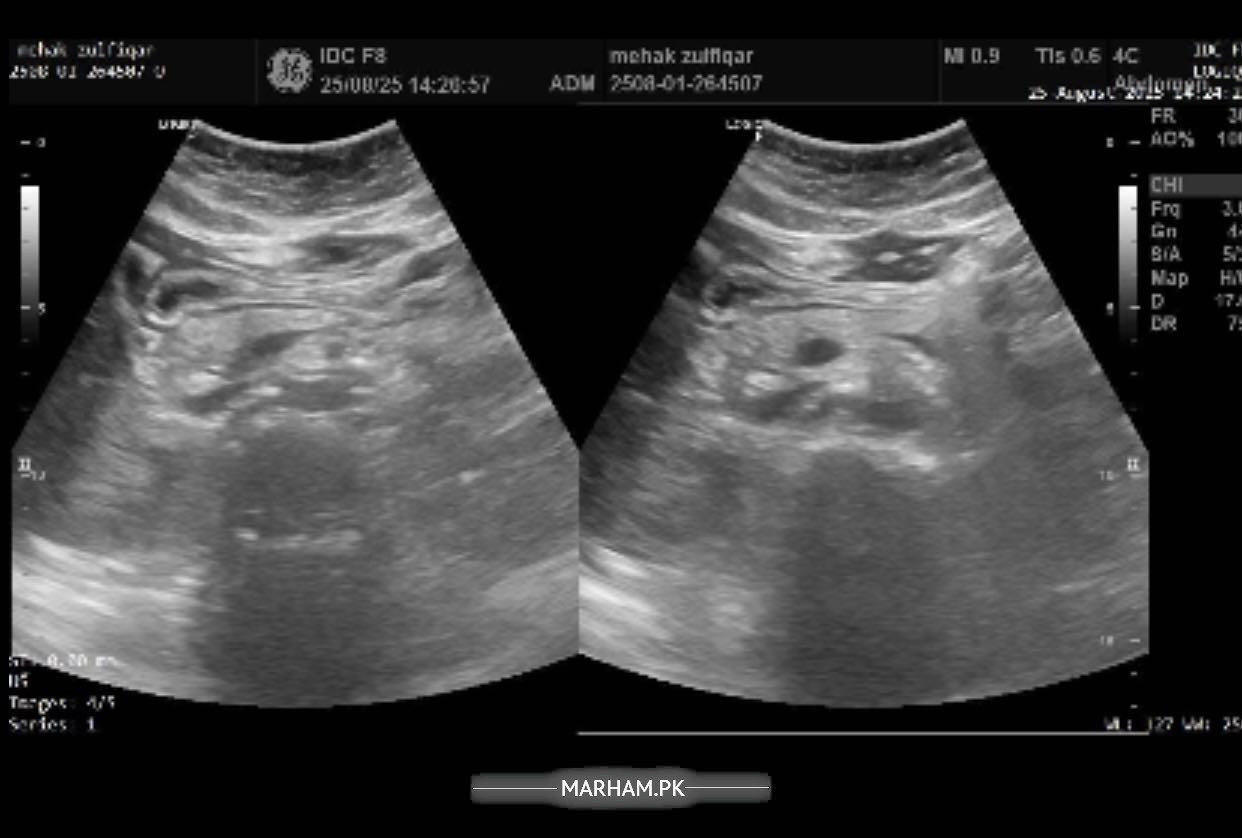

Pain in the right side of abdomen under the ribs followed by backache in the same area. In addition to these symptoms having difficulty concentrating, having confusion, difficulty speaking facial muscles hurt, sleepiness all the time, fluctuations in bp and feel nauseous with sometimes developed fever or shivering. Please help me with this. Will be highly thankful. Attached my reports too.

Sr this is the most recent ultrasound report. But radiology isn’t matching my blood reports. I am worried about that. Pls help.

Sr can’t share pics altogether but here it is

Another

report of ultrasound

you’re demonstrating features of UTI, blood in urine can be due to many things, would like to explore this in detail and get to do few more tests. I’m available for consultation

Okay I think you need proper consultation, and a proper ultrasound from a consultant. I’m available or if you want to see anybody of your liking you should. in the meantime i need you to make a record of your bp for a week, 2 readings in the morning and 2 readings at night then tell me